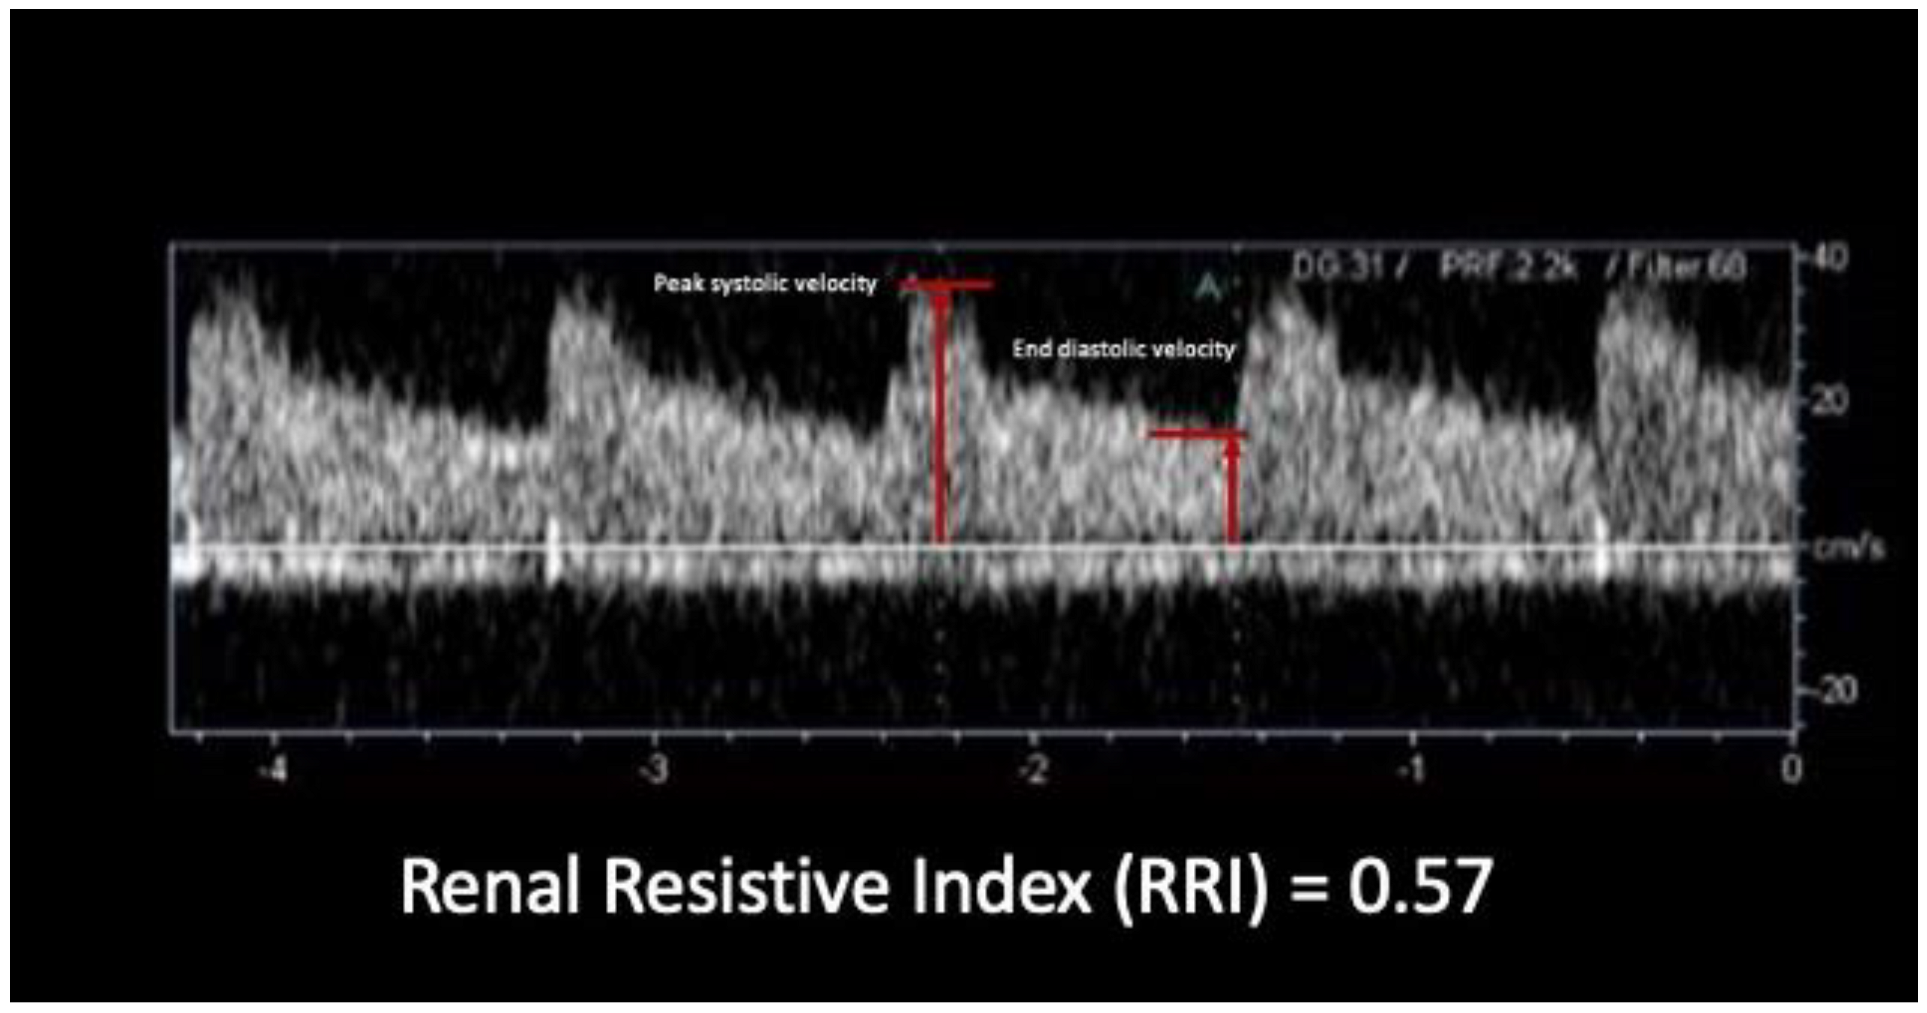

2.2. Baseline RRI Measurement

- Samoni, S.; Nalesso, F.; Meola, M.; Villa, G.; De Cal, M.; De Rosa, S.; Petrucci, I.; Brendolan, A.; Rosner, M.H.; Ronco, C. Intra-Parenchymal Renal Resistive Index Variation (IRRIV) Describes Renal Functional Reserve (RFR): Pilot Study in Healthy Volunteers. Front. Physiol. 2016, 7, 286. [Google Scholar] [CrossRef]

- Tublin, M.E.; Bude, R.O.; Platt, J.F. Review. The resistive index in renal Doppler sonography: Where do we stand? AJR Am. J. Roentgenol. 2003, 180, 885–892. [Google Scholar] [CrossRef]